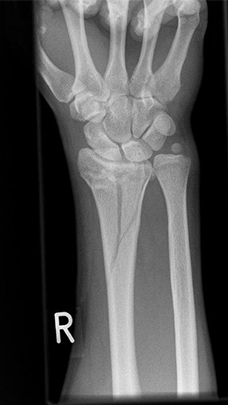

Radiusfraktur vor Korrekturoperation mit anhaltende beugeseitige Verschiebung der Handwurzel

Radiusfraktur vor Korrekturoperation: Die beugeseitige Knochenlippe ist über die liegende Platte hinweg verschoben.

Komplexe rechtsseitige Unterarm-Handgelenksfraktur

Komplexe rechtsseitige Unterarm-Handgelenksfraktur, seitlich